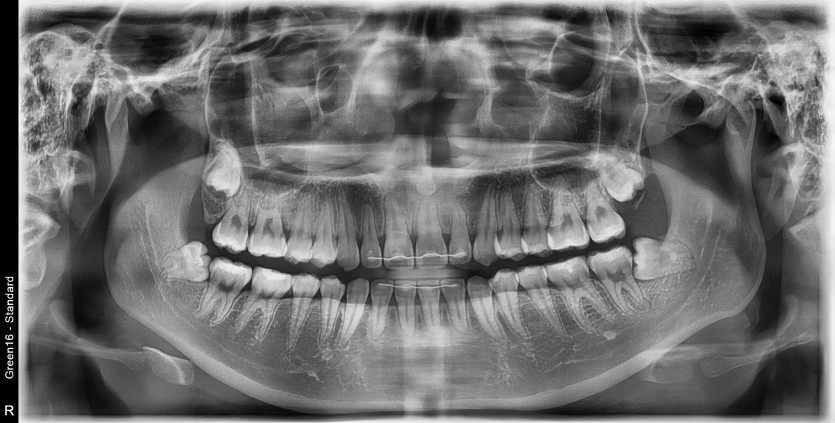

#38,48 사랑니 발치

구강 외과 전문의가 당일 발치했습니다.